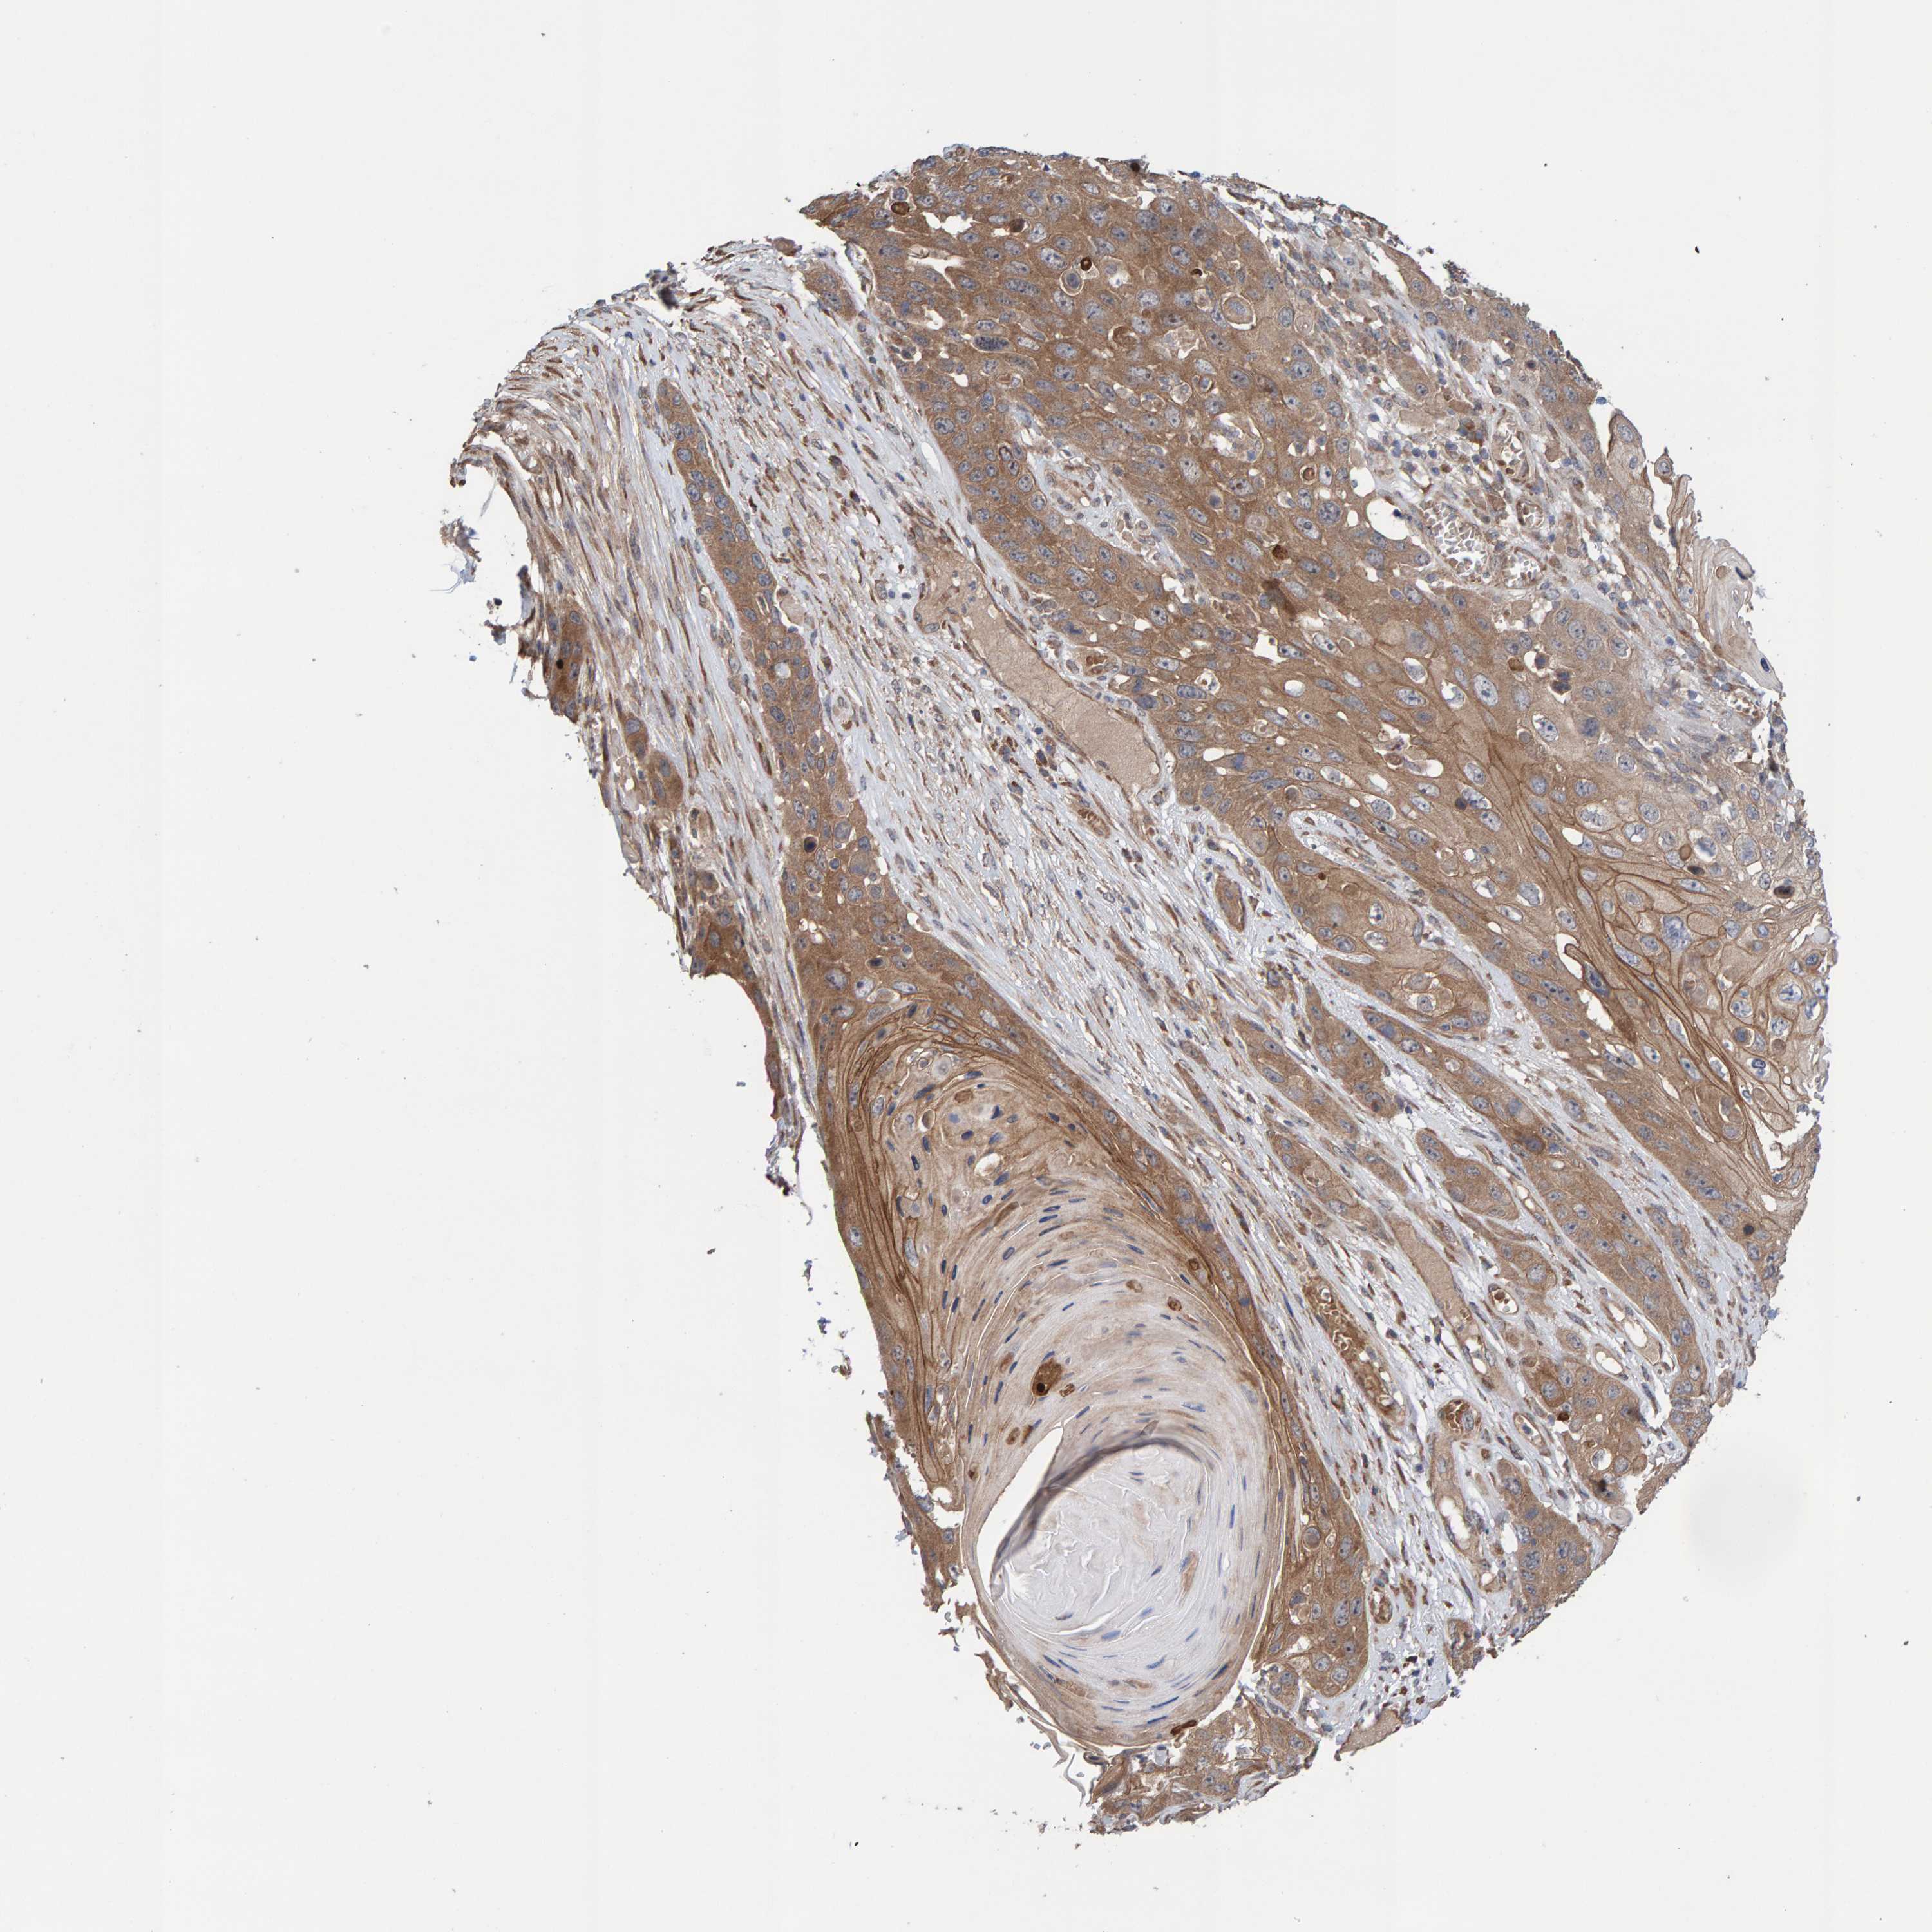

SKIN CANCER - Protein expressioni

A mouse-over function shows sample information and annotation data. Click on an image to view it in a full screen mode. Samples can be filtered based on level of antibody staining by selecting one or several of the following categories: high, medium, low and not detected. The assay and annotation is described here.

Antibody stainingi

Antibody staining in the annotated cell types in the current human tissue is reported as not detected, low, medium, or high, based on conventional immunohistochemistry profiling in selected tissues. This score is based on the combination of the staining intensity and fraction of stained cells.

Each image is clickable and will lead to virtual microscopy that enables deeper exploration of all samples and also displays staining intensity scores, fraction scores and subcellular localization as well as patient and tissue information for each sample.

Antibody HPA021844

Squamous cell carcinoma, NOS